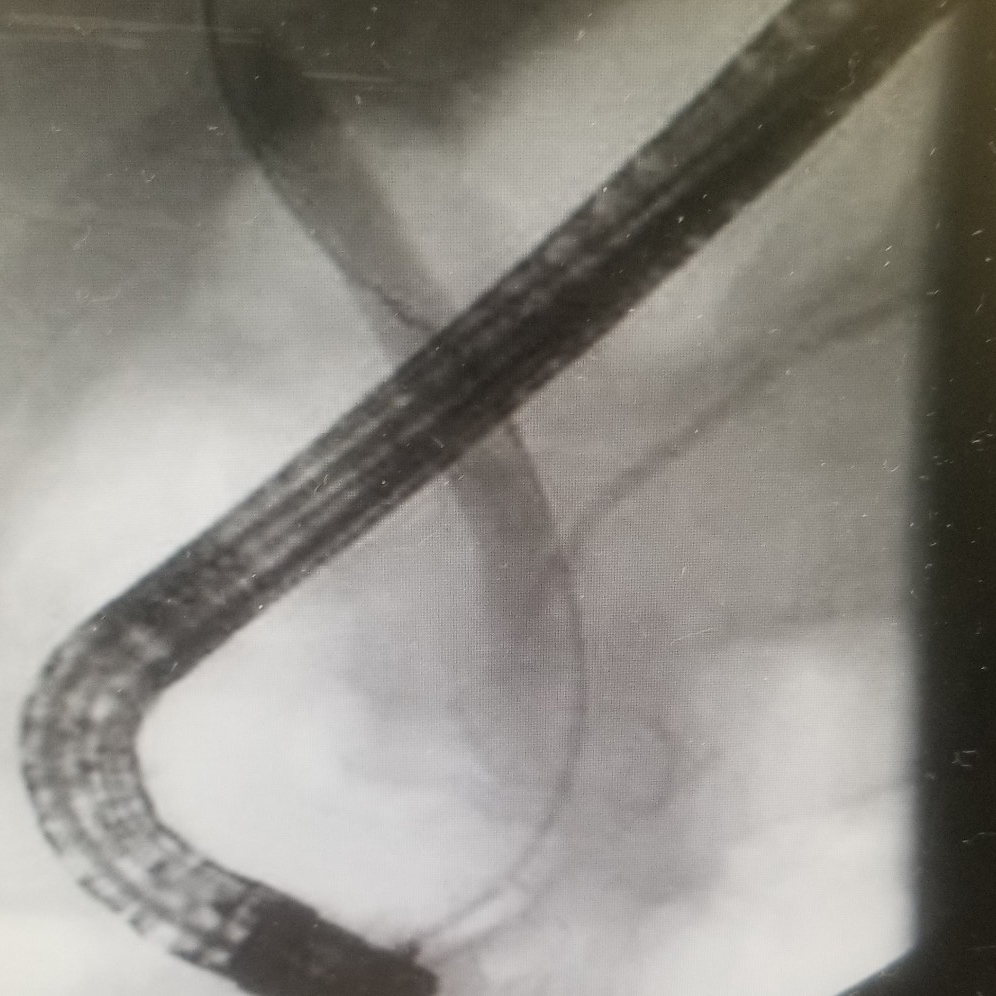

- ERCP

- Sphincterotomy, CBD, PD and cystic duct stenting, altered anatomy with lap assist

- Rendezvous

- EUS and IR guided

- Spyglass choledochoscopy